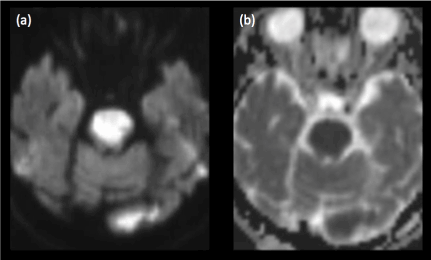

Air embolism can cause infarctions in the posterior circulation. Other potential mechanisms of infarction include arterial perforation causing thrombosis, needle-induced vasospasm, intra-arterial corticosteroid injection and arterial dissection, similar to mechanisms of spinal infarction [4]. Brain infarcts invariably involve the cerebellum, brainstem (Figures 5, 6a and 6b) or posterior cerebral artery territory.  Involvement of the optic radiation and lateral geniculate body would result in hemianopsia while involvement of the thalamic nuclei would cause hemisensory loss. Other possible presenting symptoms include vertigo, ataxia, syncope and dysarthria.

Figure 6. (a)Diffusion-weighted imaging and (b)corresponding ADC map reveal an acute pontine infarct in a patient with sudden onset of weakness post transforaminal steroid injection for symptomatic treatment of cervical spondylosis

MR imaging is excellent in depicting brain infarcts, diffusion-weighted imaging being the most sensitive in the acute settings. Infarcted brain parenchyma would be hyperintense of T2-weighted images and hypointense on T1-weighted images, due to the presence of cytotoxic oedema.